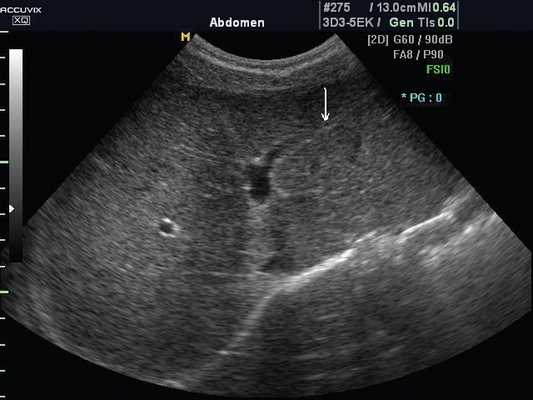

а) Эхограмма печени 12-летнего подростка в обычном режиме. Обратите внимание, что даже в 12-летнем возрасте круглая связка печени (стрелка), отходящая от левой части воротной вены, имеет каналикулярный вид (просвет внутри).

Под диафрагмой справа визуализировалось гиперэхогенное опухолевидное образование несколько неоднородной солидной структуры, с четкими ровными контурами, размером 50x38x35 мм. К нижнему полюсу данного образования прилежала правая почка, имеющая нормальные размеры, форму и структуру. Нижняя полая вена была смещена кпереди и влево. Обращала на себя внимание выраженная гепатомегалия, причем структура печени не была однородной. Она содержала множественные гиперэхогенные включения размерами до 17 мм, окруженные тонким гипоэхогенным периферическим ободком. Цветовое допплеровское картирование(ЦДК) демонстрировало интенсивную периферическую васкуляризацию опухоли (рис. 1-3).

Рис. 1. Нейробластома правого надпочечника плода. Беременность 31 нед 4 дня.